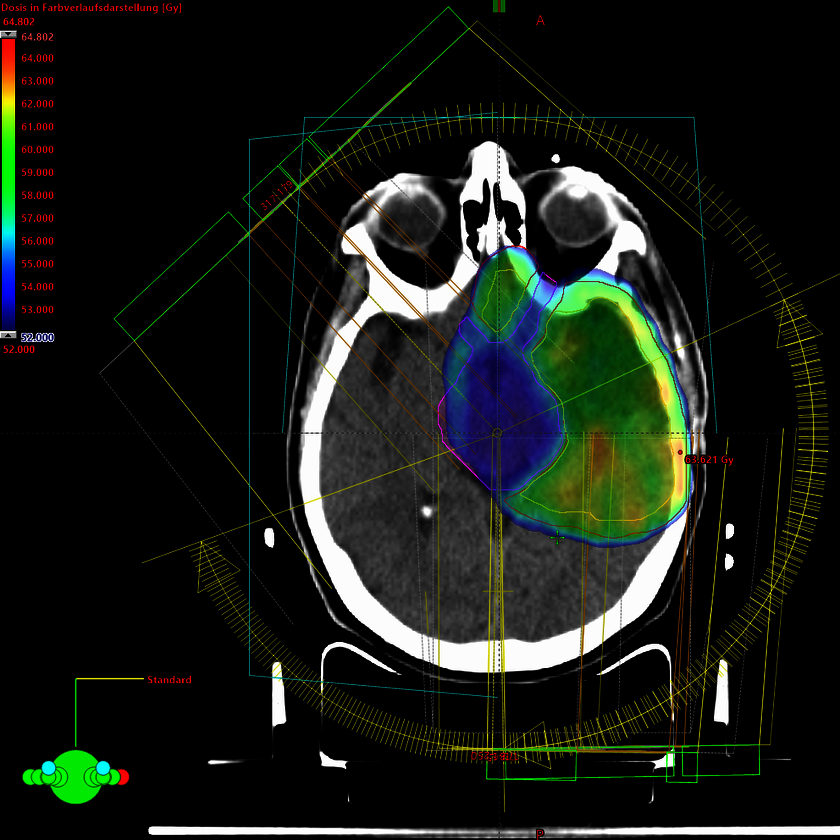

Behandlungsplan Kopf-Hals-Region mit unterschiedlichen Dosisstufen (durch unterschiedliche Farben dargestellt).

Die Behandlung von Tumoren der Kopf-Hals-Region erfolgt in der Regel als intensitätsmodulierte Radiotherapie (IMRT) oder als intensitätsmodulierte Bogentherapie (Rapid Arc®) in parallel verabreichten unterschiedlichen Dosisstufen (sogenannter simultan integrierter Boost / SIB)